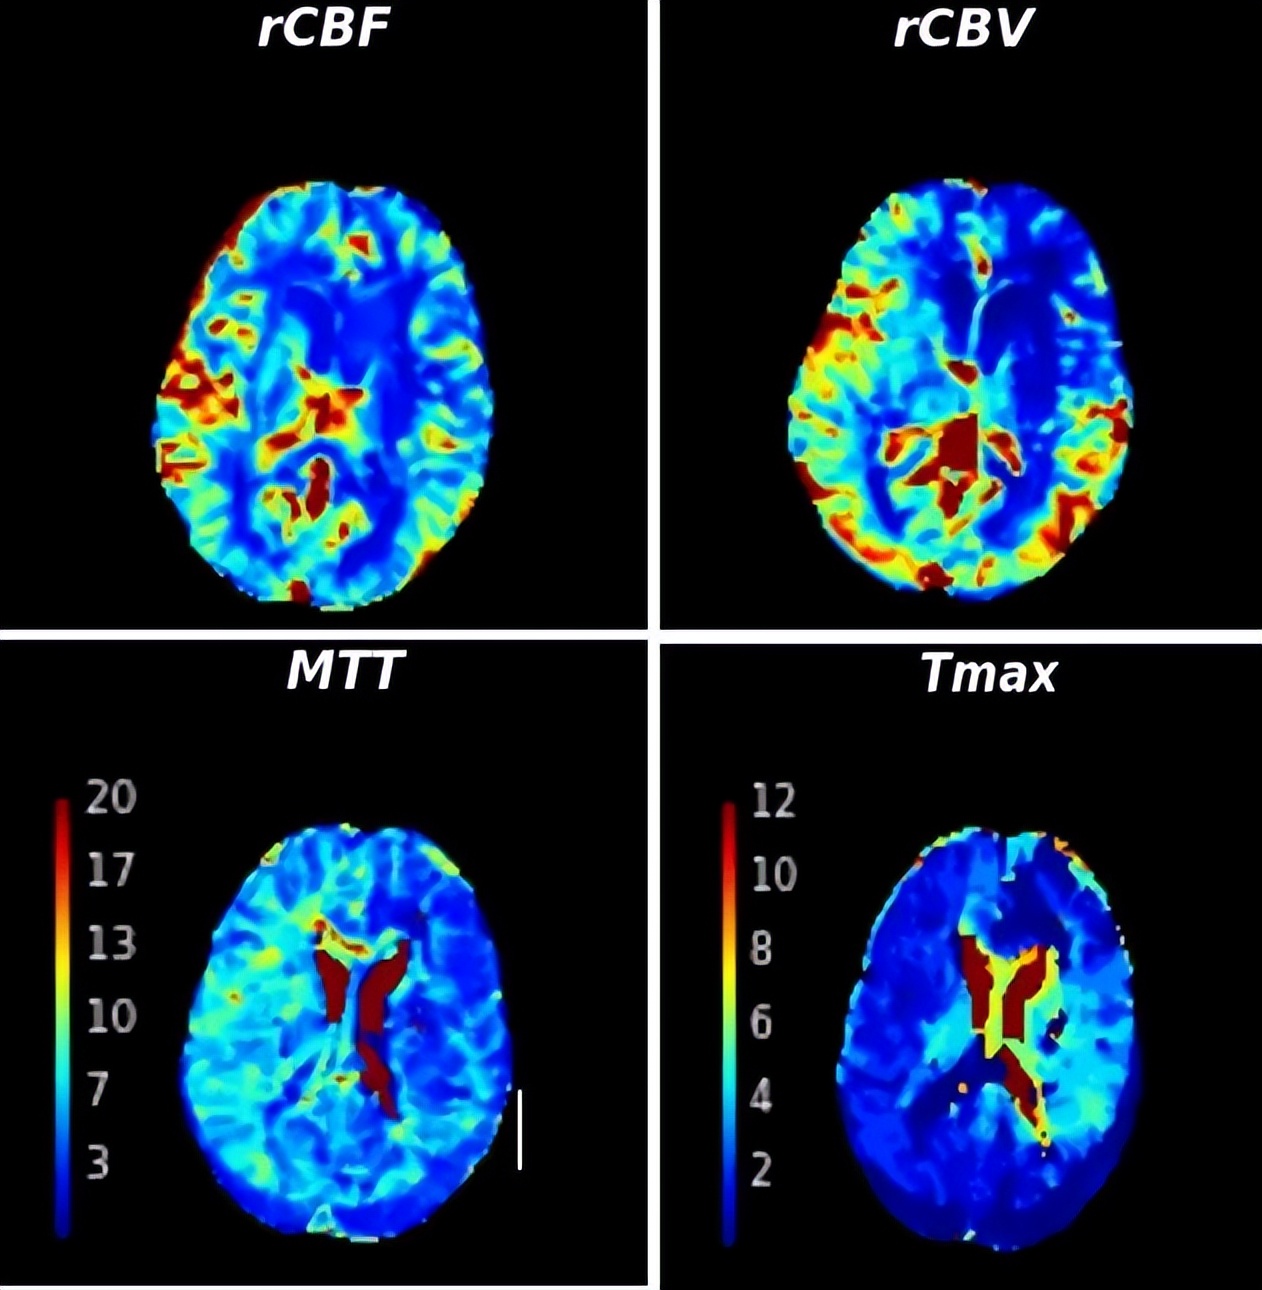

脑灌注MR

脑科中心团队采用基于PR的多模态ICAS评估系统为其进行评估:脑血管造影显示其动脉M1段狭窄程度约为65%,磁共振灌注检查显示有脑灌注不足表现,高分辨头颅MR提示狭窄出斑块不稳定,PR检测提示压力比值仅有0.59。经过上述精准评估,王女士大脑中动脉的狭窄处被判定为不稳定斑块,并且已经影响到脑灌注和脑血流,如果保守治疗的话,后期的再发脑卒中几率很大,最终王女士和家人决定接受血管内介入治疗。术中,脑科中心团队采用球囊将动脉M1段狭窄处扩展开来,PR值上升到0.76;再置入一枚颅内支架后,PR进一步上升到0.86。